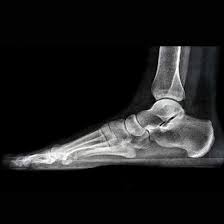

An X-ray Both Feet Lateral View helps detect fractures, deformities, infections, arthritis, and other abnormalities in the feet. It provides clear side images to assist doctors in accurate diagnosis and effective treatment planning.

An X-ray Both Feet Lateral View is a diagnostic imaging test that captures side (lateral) images of both feet. It helps doctors evaluate the bones, joints, and soft tissues to detect fractures, deformities, infections, or other abnormalities affecting the feet.